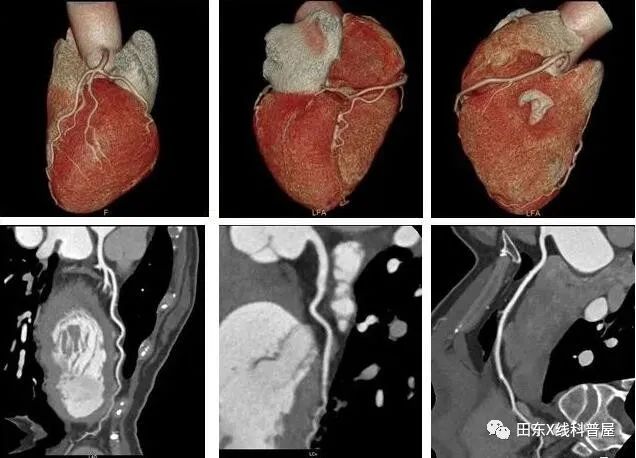

临床观察与X线检查见直背扁胸或漏斗胸改变,心底部可闻及杂音。并要排除器质性心脏病,如肺动脉瓣狭窄、房缺、室缺、特发性肺动脉扩张等。

直背综合征属于一种体质性的假性心脏病。尤其是对于年轻患者出现轻微心悸、胸闷、胸痛等症状时,在排除器质性心脏病的存在后,结合临床症状、心脏彩超、心电图及胸部X线等检查,可考虑本病。应常规行胸部正、侧位X线片检查,了解胸骨、胸椎情况,以免误诊。

治疗:轻者无需治疗,仅需适度增加体力锻炼以加强运动能力来减轻症状。重者,应考虑通过外科手术矫正其基础骨骼畸形。